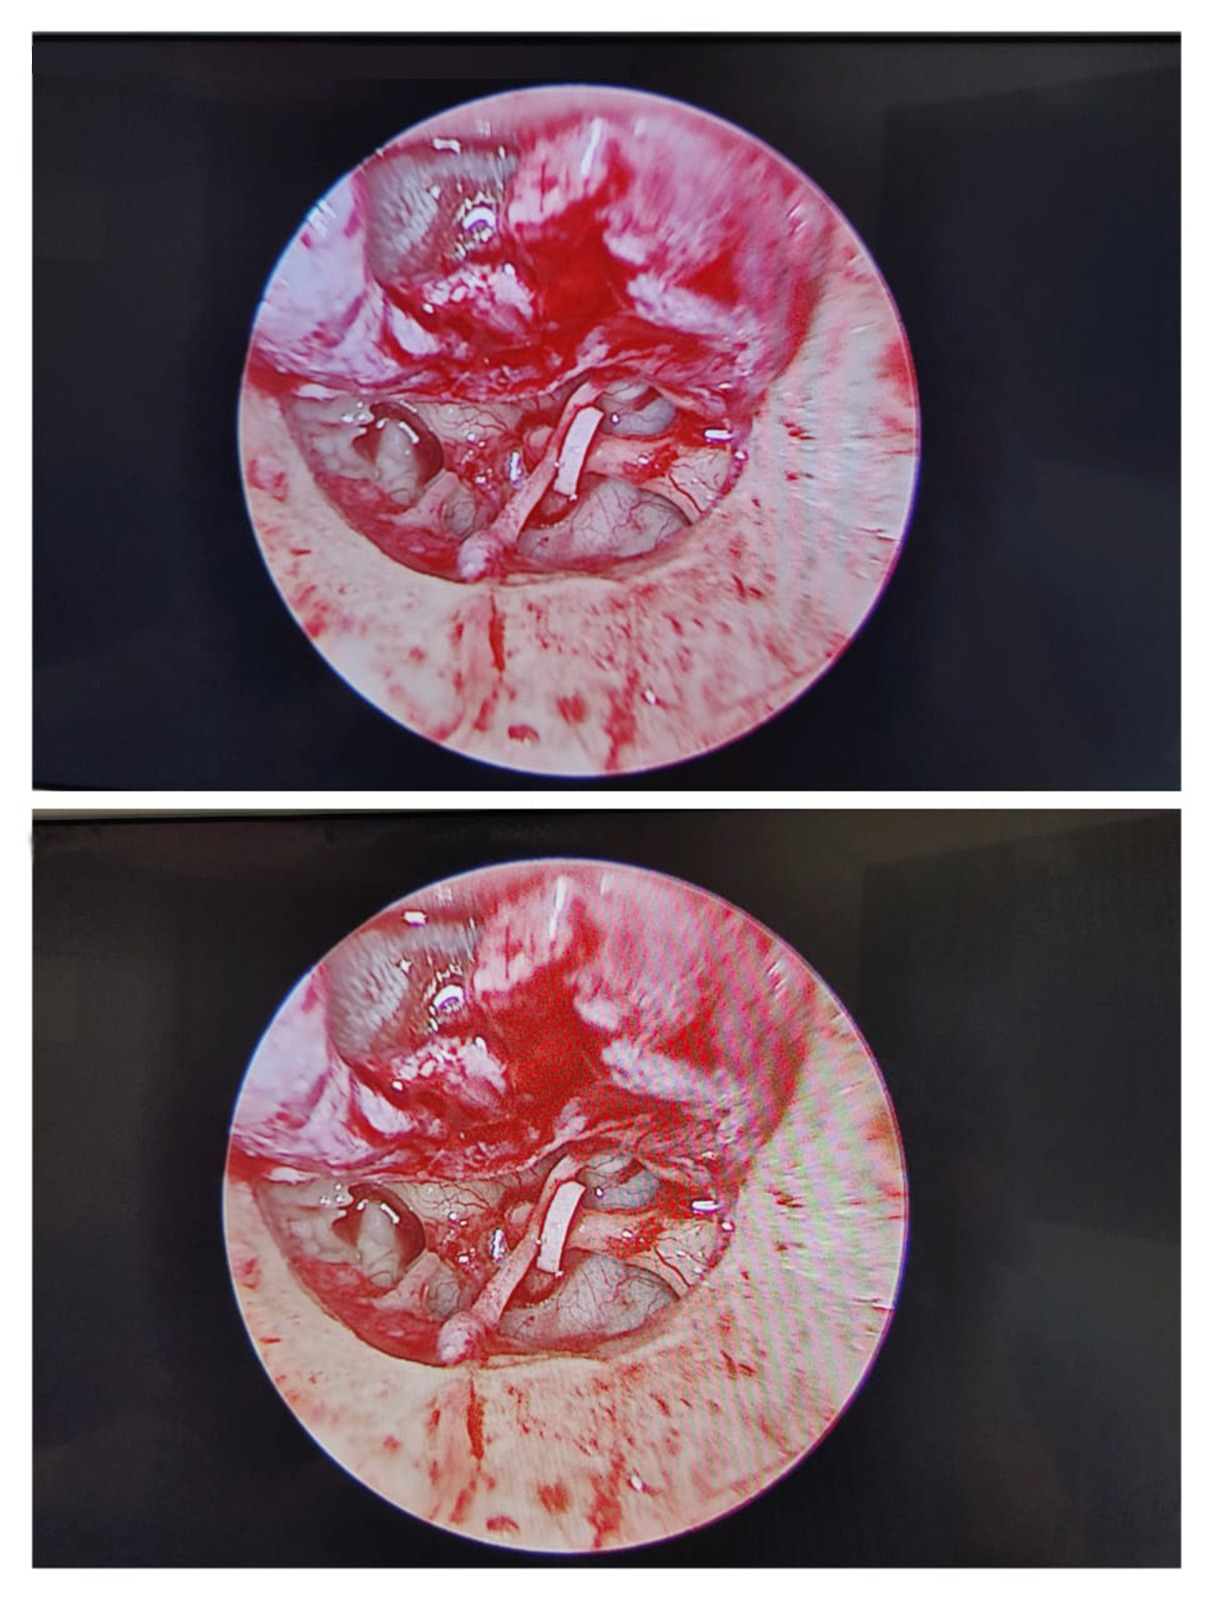

2. Stapedotomy (Otosclerosis Hearing Surgery)

Stapedotomy is performed when the stapes bone becomes fixed due to otosclerosis, causing hearing loss.

Dr. Muddazir replaces the fixed stapes bone with a prosthetic, restoring natural sound conduction.

Ideal for:

- People with progressive conductive hearing loss

- Patients with a family history of otosclerosis

Benefits

- High success rate

- Rapid hearing improvement

- Minimal discomfort

3. Ossiculoplasty (Middle Ear Bone Reconstruction)

Ossiculoplasty reconstructs or replaces damaged ossicles (hearing bones: malleus, incus, stapes).